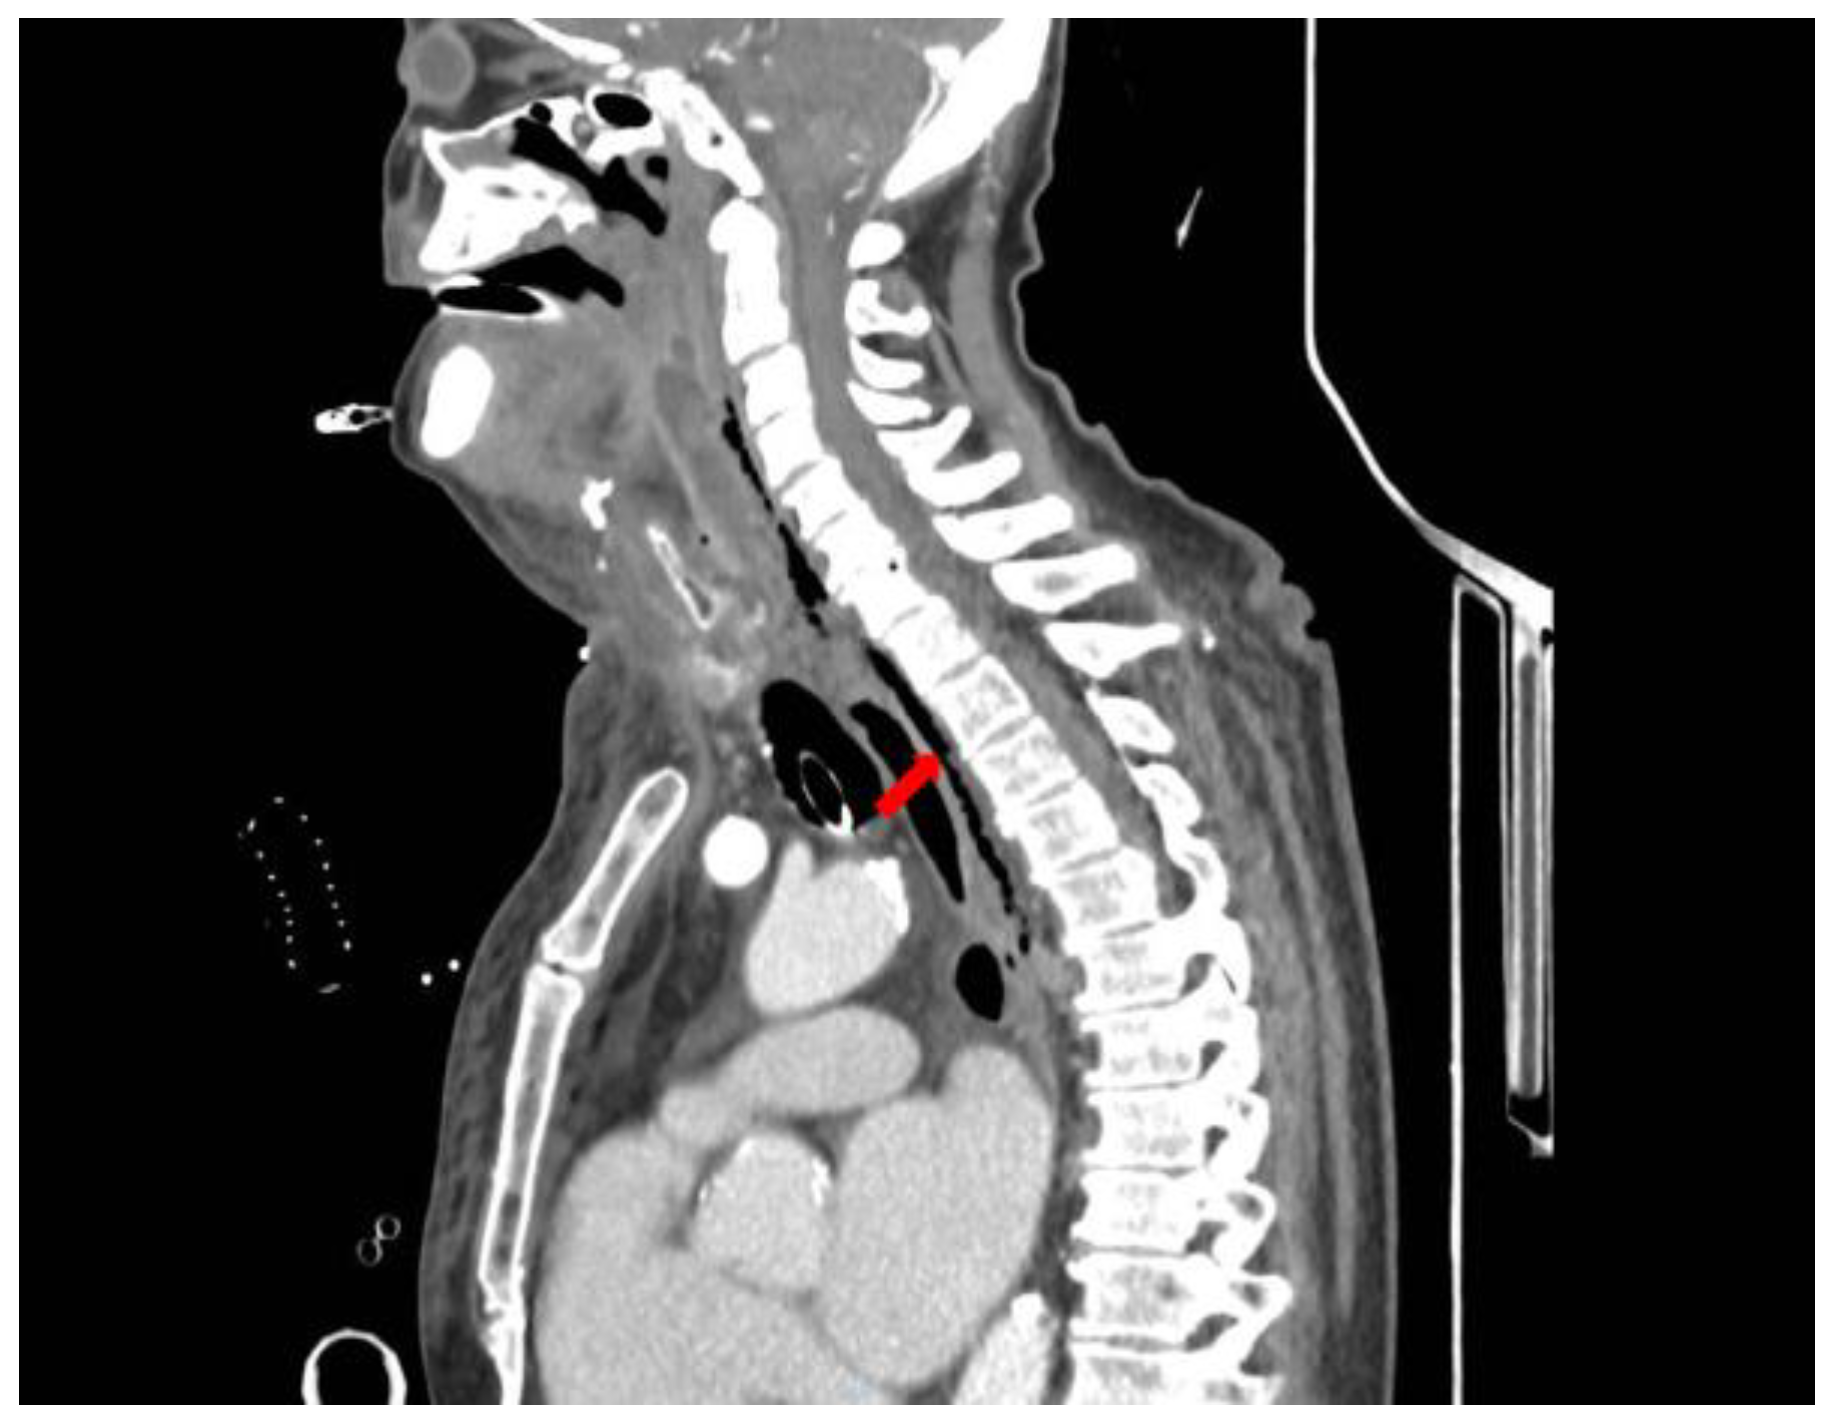

A CT scan of the head, neck, and chest with intravenous contrast, revealed a retrotonsillar fluid collection, with a maximum diameter of 10 cm, extended anteriorly to the right lobe of the thyroid gland (Figure 1). Air bubbles and minimal fluid were present from the right submandibular area to the lower mediastinum between the spine, the descending thoracic aorta, and the trachea (Figure 2).

Figure 2.

Chest CT scan with contrast material shows air bubbles and minimal fluid in the posterior mediastinum between the spine, the descending thoracic aorta, and the trachea (red arrow).